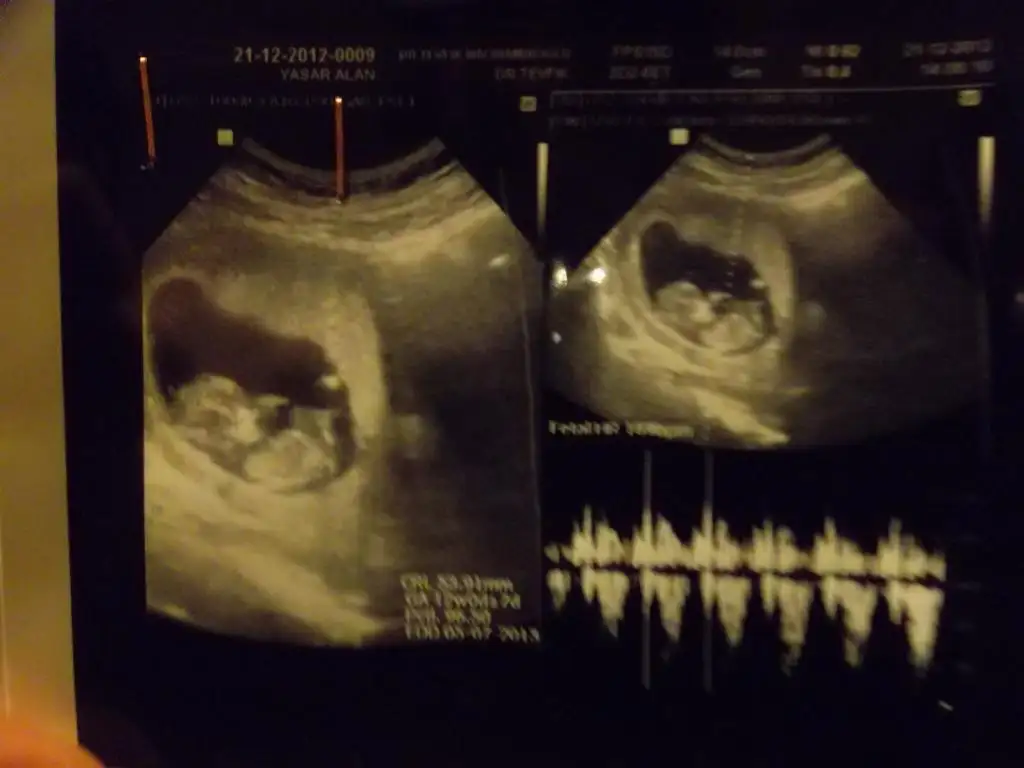

dr soylemeden siz gorun genital nub teorisi ( bebegin cinsiyeti)

kızlar bu da benimkinin son resmi :)) doktor erkek olabilir belki dedi orası çok karışık ama net bişey söyleyemem dedi bide siz bakın bakalım benim de içime hep kız doğuyordu çini rusu musu hepsinde de kız çıkıyordu bilemedim bende şimdi :))

kızlar doktor erkeğe benzetiyorum dedi ama nub bana paralel geldi sanki :44::44:

aslinda resmin tahmin icin uygun degil popsu asagida olmali tahmin icin ama bana cok parallel geldi, eger 13 haftada gittiysen bu nub kiz nubu:) ama onceden gittiysen aci degisebilir sonradan.

pardon alinti yapinca resmini daha net gordum aksine yukari dogru aci var sanki ama iste pozisyonu yanlis, pozisyona gore nubun gorunusu degisiyor.